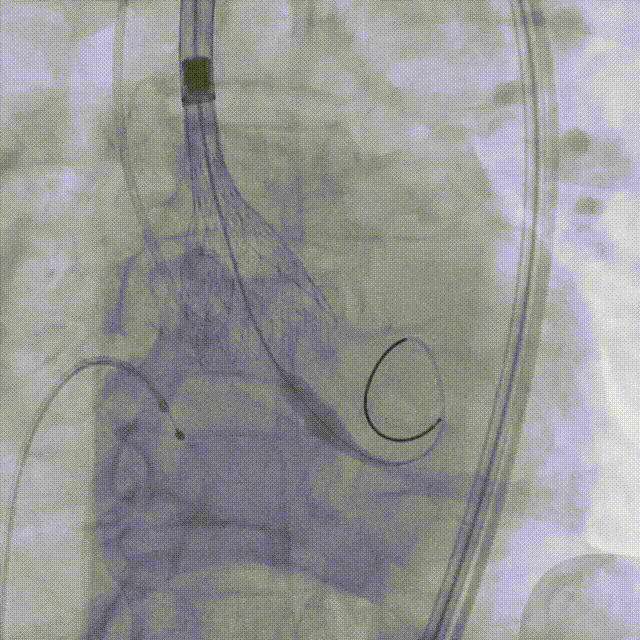

20mm球囊第一次预扩张 钙化太重,球囊卡腰征

20mm球囊第二次预扩张 球囊完全扩张开,达到扩张目的

5. 植入26mm Evolut PRO瓣膜

瓣膜释放到2/3的位置(手柄上有触觉提示)

瓣膜释放到80%并造影评估深度合适(少量反流,瓣膜形态椭圆)

左冠切线位造影评估冠脉风险(左冠血流灌注良好)

22mm球囊后扩张(瓣膜形态更佳)

最终造影(反流微量)